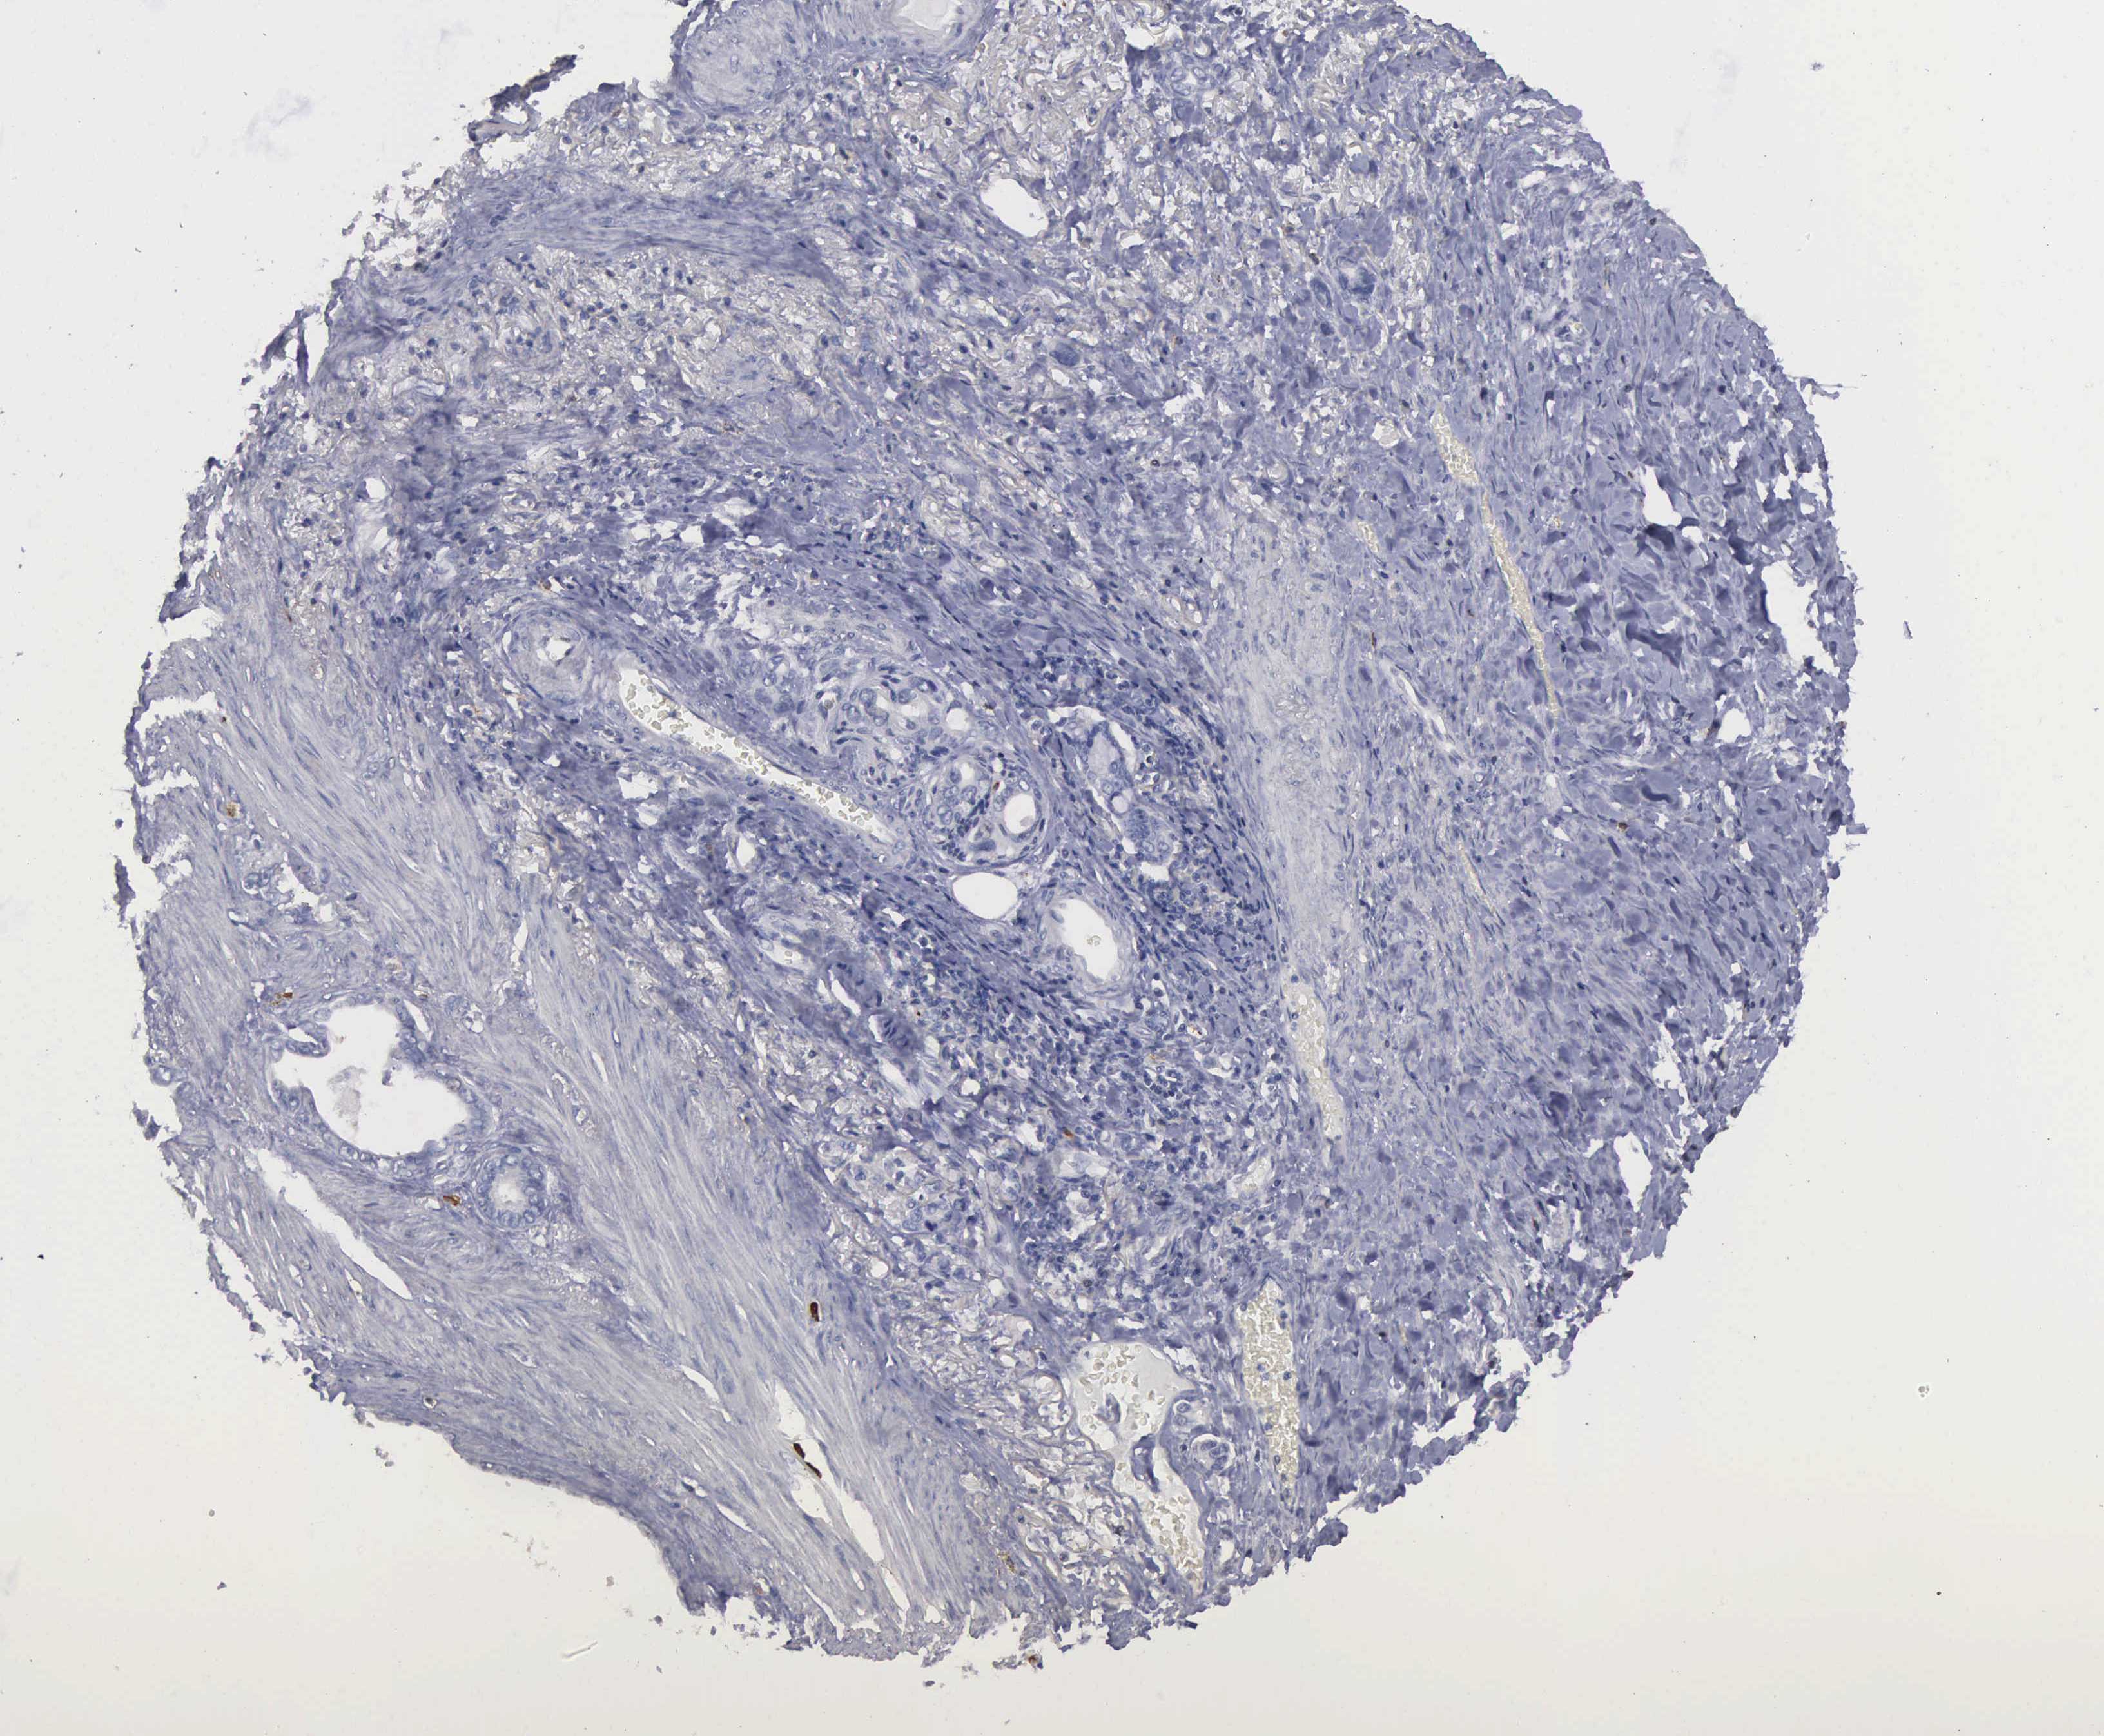

STOMACH CANCER - Protein expressioni

A mouse-over function shows sample information and annotation data. Click on an image to view it in a full screen mode. Samples can be filtered based on level of antibody staining by selecting one or several of the following categories: high, medium, low and not detected. The assay and annotation is described here.

Note that samples used for immunohistochemistry by the Human Protein Atlas do not correspond to samples in the TCGA dataset.

Antibody stainingi

Antibody staining in the annotated cell types in the current human tissue is reported as not detected, low, medium, or high, based on conventional immunohistochemistry profiling in selected tissues. This score is based on the combination of the staining intensity and fraction of stained cells.

Each image is clickable and will lead to virtual microscopy that enables deeper exploration of all samples and also displays staining intensity scores, fraction scores and subcellular localization as well as patient and tissue information for each sample.

Antibody HPA000793

Staining

High

Medium

Low

Not detected

Intensity

Strong

Moderate

Weak

Negative

Quantity

>75%

75%-25%

<25%

None

Location

Nuclear

Cytoplasmic/membranous

Cytoplasmic/membranous,nuclear

Adenocarcinoma, NOS